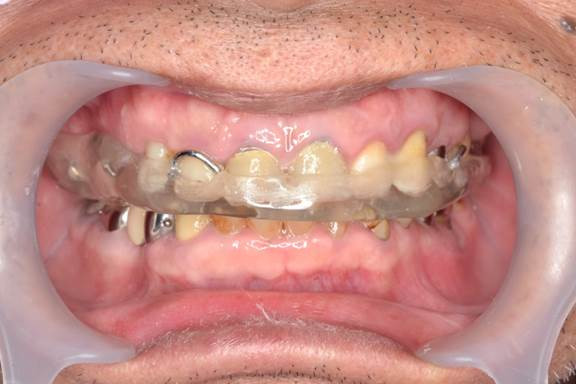

「歯ぎしり・くいしばりで歯が痛い」という相談が増えてきています。上の画像は、「歯ぎしり・くいしばり」が酷く、奥歯が数本ですが歯根破折してしまったため、抜歯を余儀なくされた患者様です。咬んだ時の力をストップさせる奥歯の本数が少なくなるにつれて、前歯に負担が大きくなるため、ハード スプリント(マウスピース)を装着した状態です。